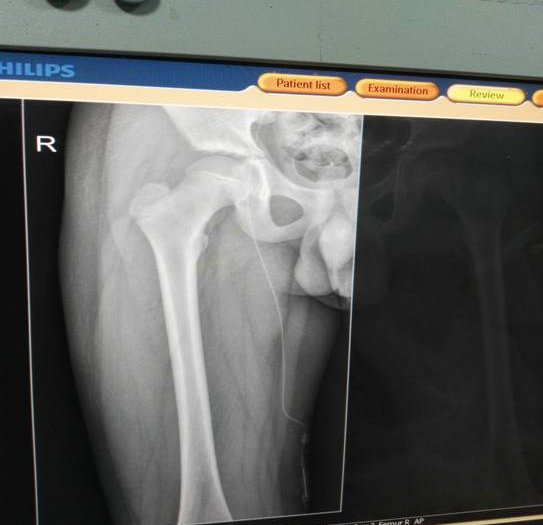

经过静疗小组详细的评估患儿实际情况后,最后决定在患儿的大隐静脉处进行穿刺置管,但该置管技术水平要求极高,操作过程较复杂,目前我市还没有哪一家医院开展该项操作技术,针对这一情况,静疗小组做好了充分准备,制定出各种应急措施,把患者目前情况与家属沟通征得家属同意后便进行穿刺置管,一针穿刺成功、置管过程顺利,X线片提示导管置于髂总静脉内,术后患儿无并发症及任何不适,并于2017年8月28日康复出院,得到了患儿家属的一致好评!